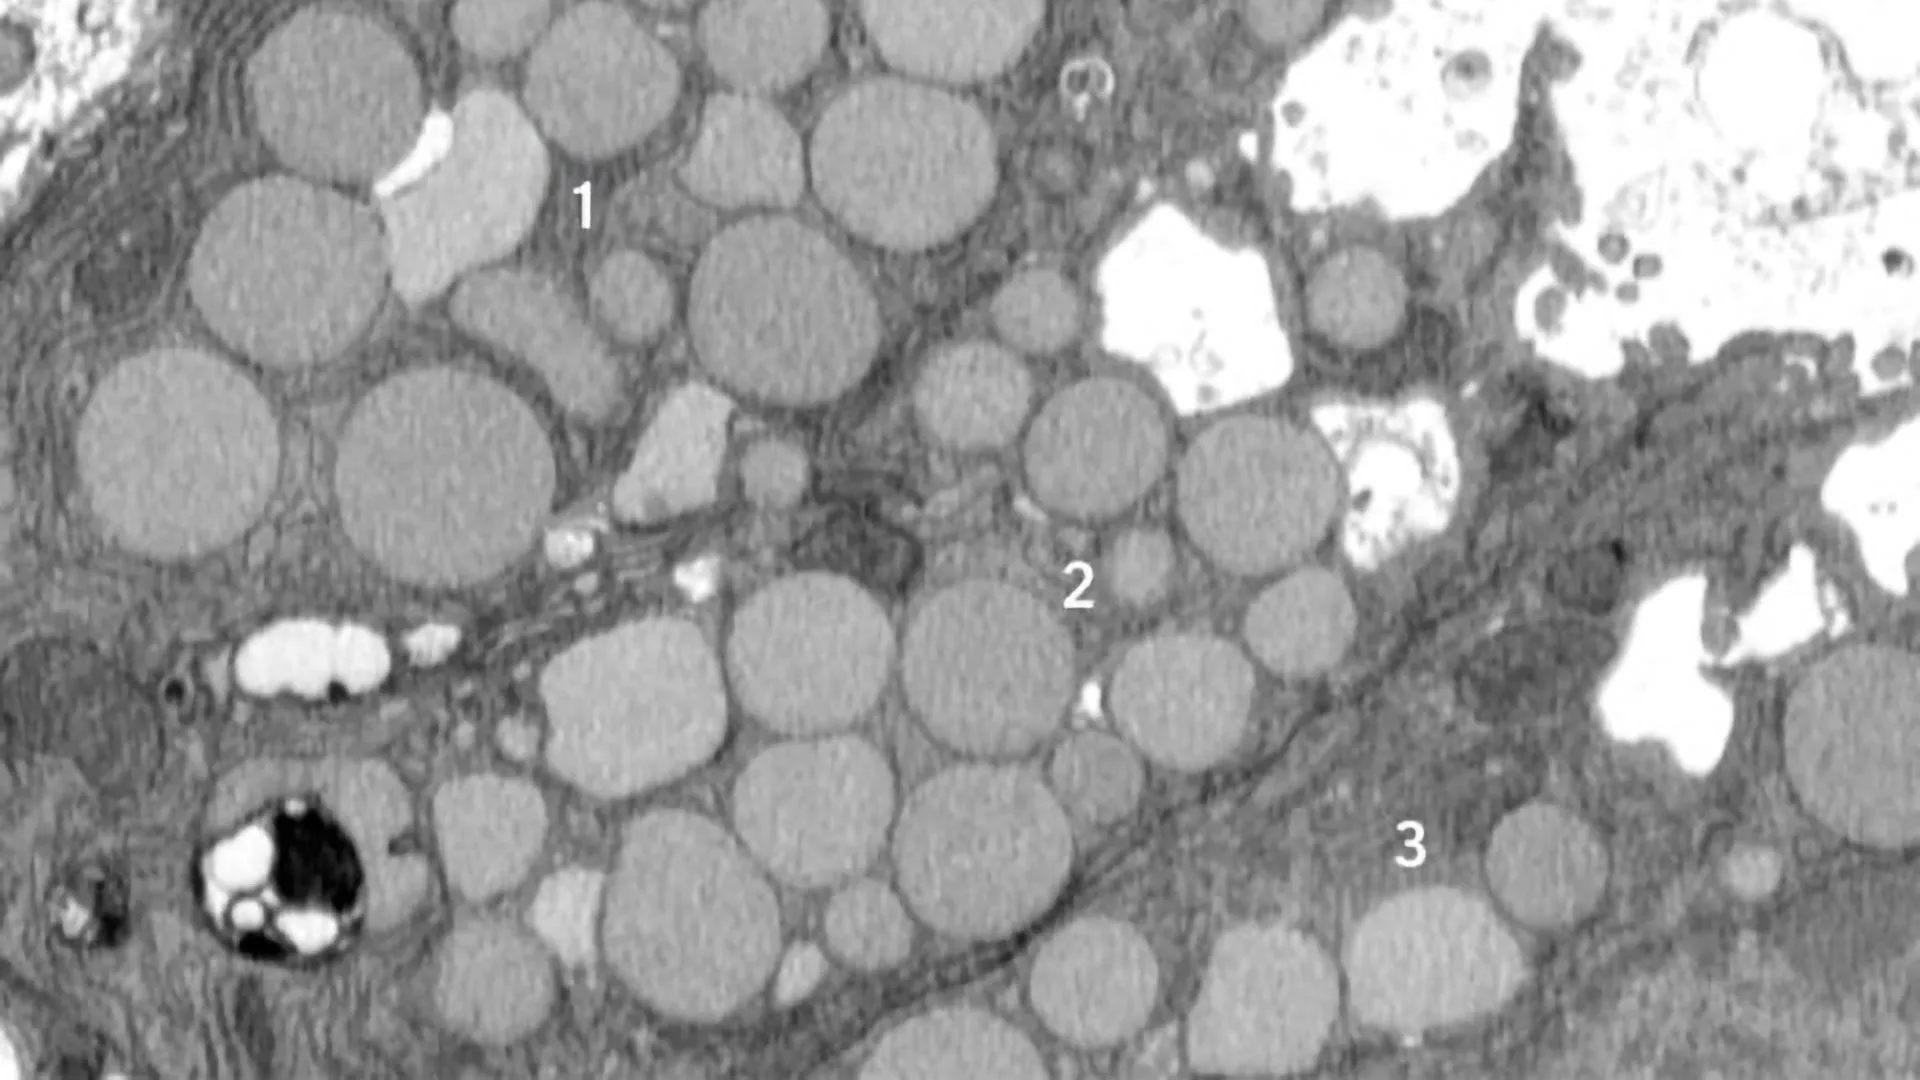

Over the past 50 years, rates of obesity and type-2 diabetes have soared, while